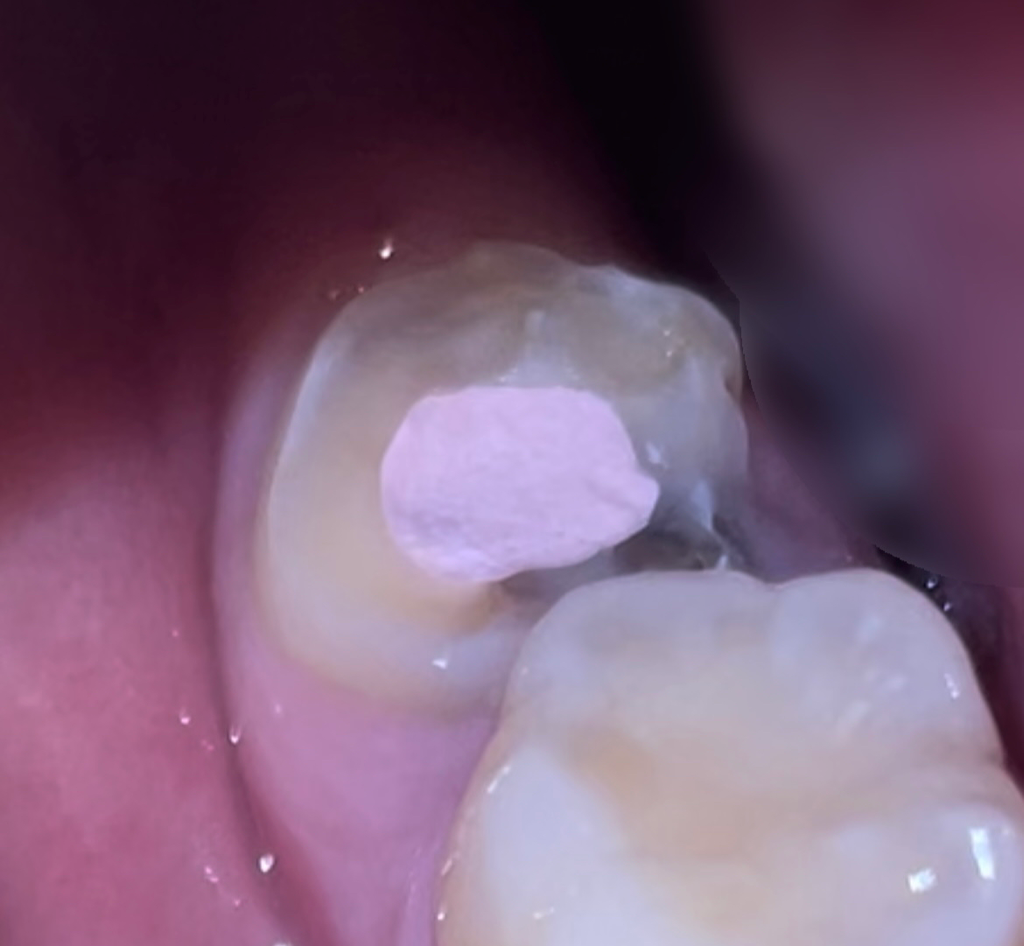

현재 제 이빨 상황인데 일주일 동안 이렇게 둬도 괜찮을까요? ㅠ ㅠ 일주일 사이에 더 안 좋아져서 막 이빨 뽑아야 되는 상황까지 갈까 봐 너무 무섭습니다..

• 1번 째 사진

치료 도중이기 때문에 지금 상태로 두셔도 됩니다. 치료 부위를 임시 재료로 막아 놓은 것이며 치료를 할 때 해당 부위를 제거하고 다시 신경치료를 진행하고 할 것입니다. 즉 치료마다 해당 임시수복재를 계속해서 사용하게 됩니다. 특별히 담당 의사 선생님이 언급이 없다면 이대로 두셔도 상관 없습니다.

일반적으로 신경치료를 하게 되면 저렇게 임시재료로 채워 놓습니다. 보통 신경치료 간격은 짧으면 3-4일 일반적으로 일주일정도 간격을 두게 됩니다. 크게 문제는 없으니 약속때 병원에 가시면될것같습니다.

신경치료 중에는 임시충전재료로 신경치료를 하는 구멍을 막아둡니다. 현재 그러한 상황이라고 생각됩니다.